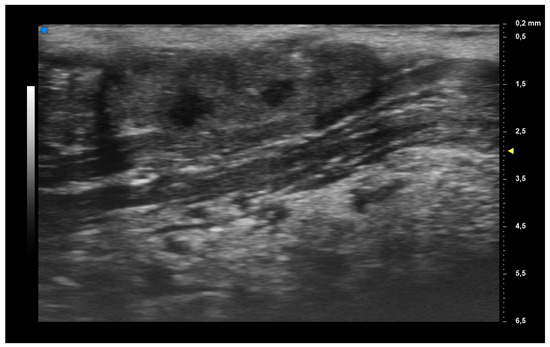

| UHFUS Characteristics | Sicca Syndrome (n = 4) | Parotitis (n = 2) | Non-Sicca, Non- Parotitis (n = 6) | Total (n = 12) |

|---|---|---|---|---|

| Grade 1 | 3 (75%) | 1 (50%) | 4 (67%) | 8 (67%) |

| Grade 2 | 0 (0%) | 1 (50%) | 1 (17%) | 2 (17%) |

| Grade 3 | 1 (25%) | 0 (0%) | 1 (17%) | 2 (17%) |

| Mild vascularization | 1 (25%) | 1 (50%) | 1 (17%) | 3 (25%) |

| Moderate vascularization | 3 (75%) | 1 (50%) | 5 (83%) | 9 (75%) |